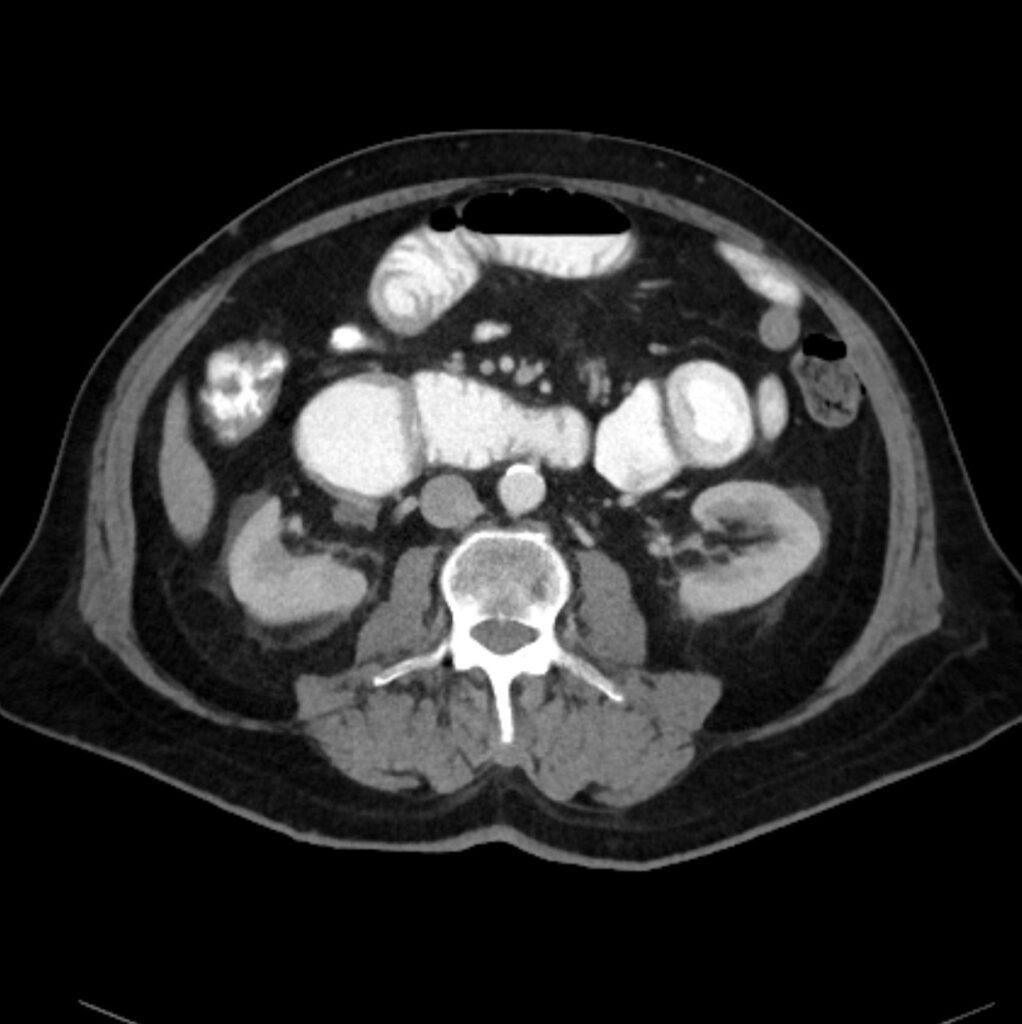

*72-year-old male with abdominal pain and vomiting.

What is the most likely diagnosis?

Answer: Small bowel mesentery internal hernia

CT images revealed the dilated loops, mesenteric edema, and beak-like point of obstruction